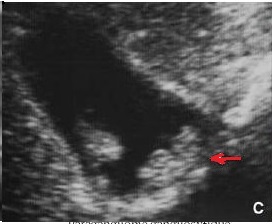

Image echographique en coupe

longitudinale de la vesicule biliaire : Aspect de

multiple formation polypoide adenomateuse

isoechogene de type pedicule ( fleche rouge ) . |